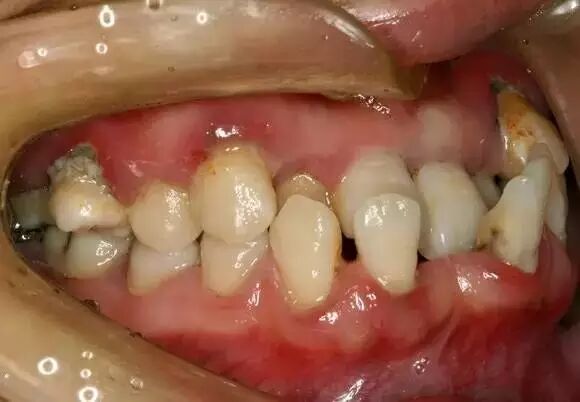

牙没有换完,不能正畸

每个人的正畸时间是不一样的,这是由于不同的牙齿、颌骨生长发育有早有晚、有块又慢。牙齿矫正本身也分很多种,比如说乳牙期的矫正、替牙期的矫正、换完牙后的成年矫正。每个人的情况不一样,方案、正畸开始时间也不一样,所以说如果在“是否能整牙”这个问题上犹豫不决,还是要先找倩婷牙醫看看再说。